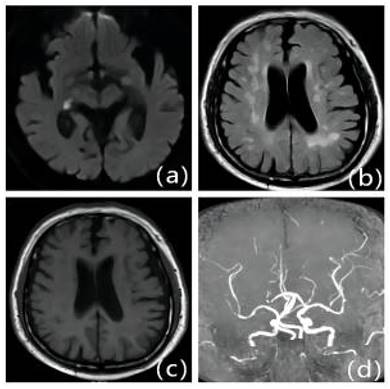

Figure 5

Patients with first IS due to ICAS with moderate LA: Female, 79 years old, admitted 6.5 hours after onset. A: DWI, B: T2WI-FLAIR, C: T1WI, D: MRA. DWI shows fresh cerebral infarction in the right temporo-occipital junction region; MRA shows multiple stenoses in the right posterior cerebrum. T2WI-FLAIR and T1WI show bilateral periventricular cerebral white matter demyelination changes.

Figure 6

Patients with first-onset IS due to ICAS with severe LA: Male, 70 years old, admitted 9 hours after onset. A: DWI, B: T2WI-FLAIR, C: T1WI, D: MRA. DWI shows right thalamic lamellar cerebral infarction; MRA shows fewer distal branches and narrowing of the right middle cerebral artery than the contralateral side. T2WI-FLAIR and T1WI show diffuse demyelinating changes in the white matter of the brain around the ventricles bilaterally.